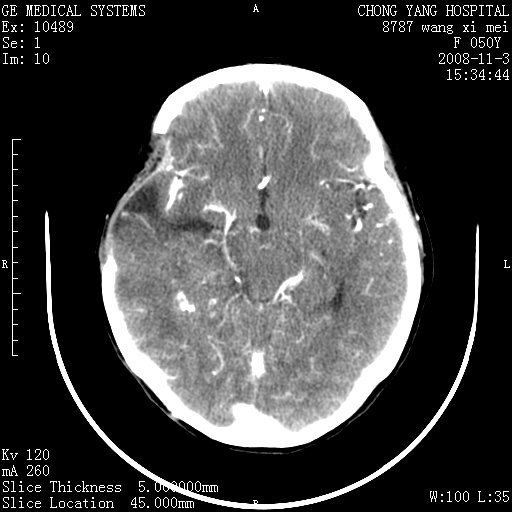

右侧颞顶部可见低密度实变影,内见不规则钙化灶,边界不清,占位效应明显,侧脑室后角受压移位,符合胶质瘤术后复发改变。

右颞骨局限性缺如,局部脑组织无外隆。右颞叶可见片状脑脊液样低密度影,边缘较清,右侧侧脑室三角区可见一块状等密度影,且伴有强化,余未见明显异常改变。

考虑:右大脑术后改变伴肿瘤复发。

手术后局部片状低密度改变(软化灶),其后方颞叶似等密度病灶,界限不清,内见钙化,有轻度占位效应,但增强后强化之血管走行如常。应不考虑:复发!

考虑右侧颞顶叶胶质瘤术后复发。

应考虑肿瘤复发,右颞顶叶已出现轻度强化肿块.必要时可与原片比较以下.

右侧颞顶部混杂密度影,内有钙化,有占位效应。应该是复发灶。结合术后片更好。